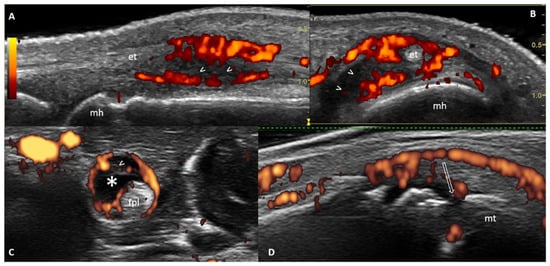

- Nam, J.L.; Hensor, E.M.A.; Hunt, L.; Conaghan, P.G.; Wakefield, R.J.; Emery, P. Ultrasound findings predict progression to inflammatory arthritis in anti-CCP antibody-positive patients without clinical synovitis. Ann. Rheum. Dis. 2016, 75, 2060–2067. [Google Scholar] [CrossRef]

- Di Matteo, A.; Mankia, K.; Duquenne, L.; Cipolletta, E.; Wakefield, R.J.; Garcia-Montoya, L.; Nam, J.L.; Emery, P. Ultrasound erosions in the feet best predict progression to inflammatory arthritis in anti-CCP positive at-risk individuals without clinical synovitis. Ann. Rheum. Dis. 2020, 79, 901–907. [Google Scholar] [CrossRef]

| Nam et al. [24] | 2016 | PS | 136 | 100% | 45% | 100% | New onset MSK symptoms | Y (48 HC) | 41.9% | Median: 18.3 M (range 0.1–79.6) | US findings (especially PD) predictive for progression to IA |

| Di Matteo et al. [32] | 2020 | PS | 419 | 100% | 38% | 100% | New onset MSK symptoms | N | 30.7% | Median: 9.9 M (IQR 3.6–26.7) | BE in >1 joint, and BE in combination with US synovitis in the MTP5 joints, most predictive for the development of IA |